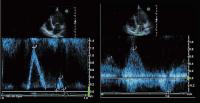

Abbildung 2: Sogenannter "diastolischer shudder" des vorderen Mitralsegels in der M-Mode-Registrierung (parasternal lange Achse)

Abbildung 4: CW-Dopplersignal der aortalen Regurgitation mit kurzer Druckhalbwertszeit